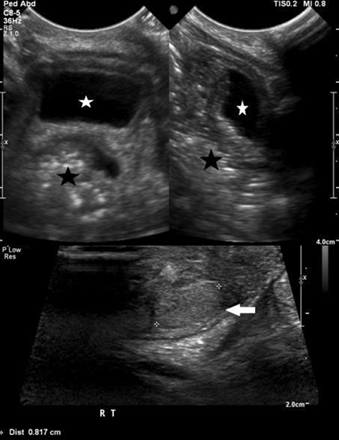

During the period under review, a total of 69 patients with 46 xy dsd were evaluated. Twelve (20.3%) patients, were diagnosed to have 5-α-reductase deficiency, based on hormonal investigations, the (dht/t) ratio, post-hcg stimulation, was high in all patients. Their ages ranged from birth to 12 years. The diagnostic imagings (ultrasound and/or magnetic resonance mr) were utilized to elucidate the internal organs (figures 2 and 3). None of the patients were found to have internal female structures. However all were found to have testes in variable positions (abdomen, inguinal canal and scrotum).

Establishing the diagnosis of 5-α-reductase deficiency is often suggested by an elevated plasma testosterone (t), to dihydrotestosterone (dht) ratio following human chorionic gonadotropin hormone (hcg) stimulation8-10. Genetic studies can confirm the diagnosis11-16. Imaging diagnostic studies with ultrasonography (us) and/or magnetic resonance (mr) will help in elucidating the internal structures. In all patients no female internal organs were demonstrated, however, all were found to have testes in variable positions (abdomen, inguinal canal and scrotum)17-24.